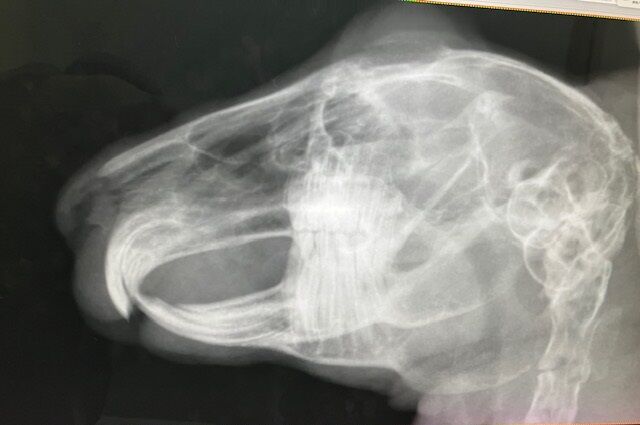

術前の血液検査、レントゲン、いずれも問題ありません。

※白血球の上昇などはストレス起因と判断できるレベル、と、

血小板は機械の誤作動による、顕微鏡で別途確認済

奥歯も問題なし。

12月4日、ドナちゃん避妊手術しました。